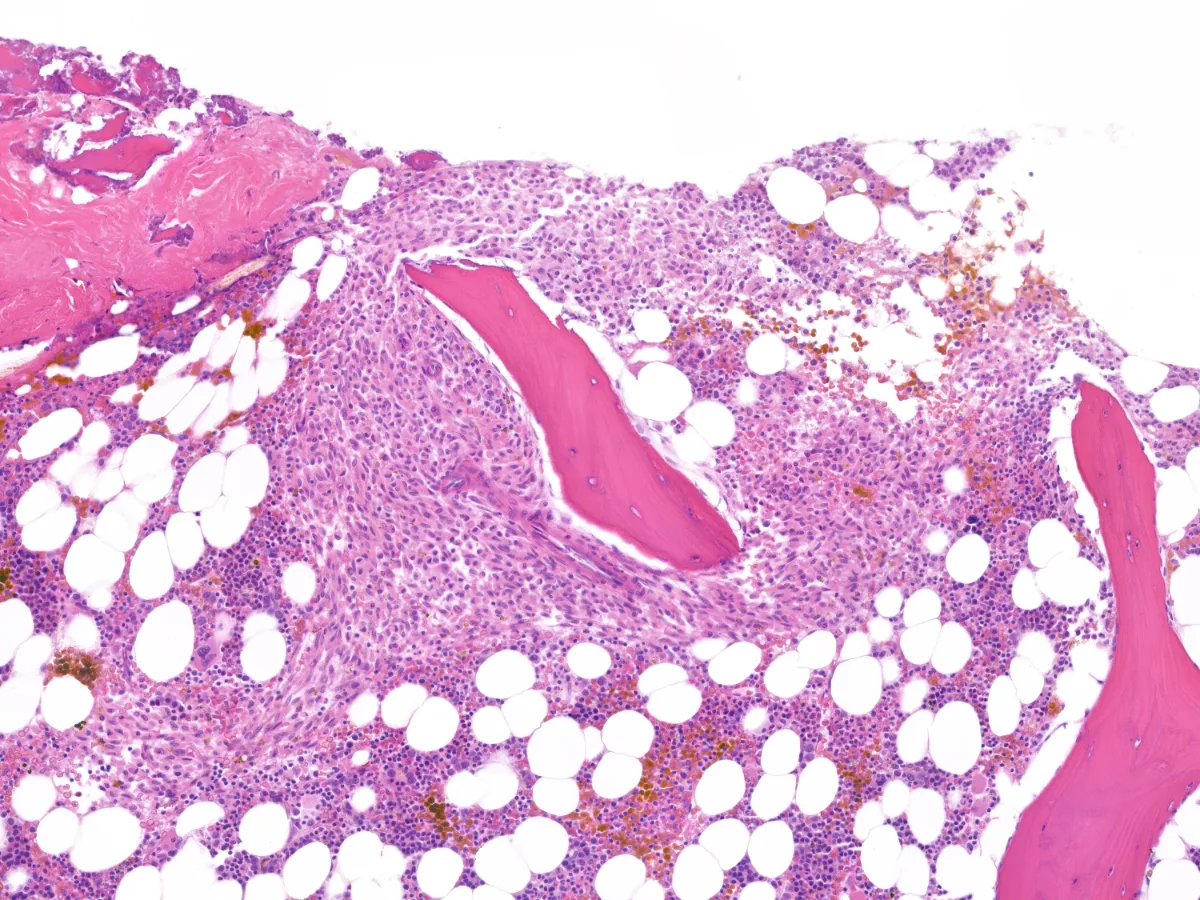

En el estudio de extensión se objetiva una Triptasa sérica elevada (181 µg/l), así como mutación en KIT p.D816V en sangre periférica. Se realiza biopsia de médula ósea…

Imágenes:

1. HE 2x

Diagnóstico: Mastocitosis sistémica asociada a neoplasia hematológica (Policitemia Vera).

- Para el diagnóstico de mastocitosis sistémica (MS) es necesario el análisis citohistológico de una biopsia o aspirado de médula ósea, siendo el criterio mayor la presencia de agregados de >15 mastocitos en médula ósea u otros órganos extracutáneos y los criterios menores una morfología atípica, las mutaciones en KIT, una triptasa sérica elevada y un inmunofenotipo aberrante (incluyendo CD2, CD25 y CD30). PMID: 34901755